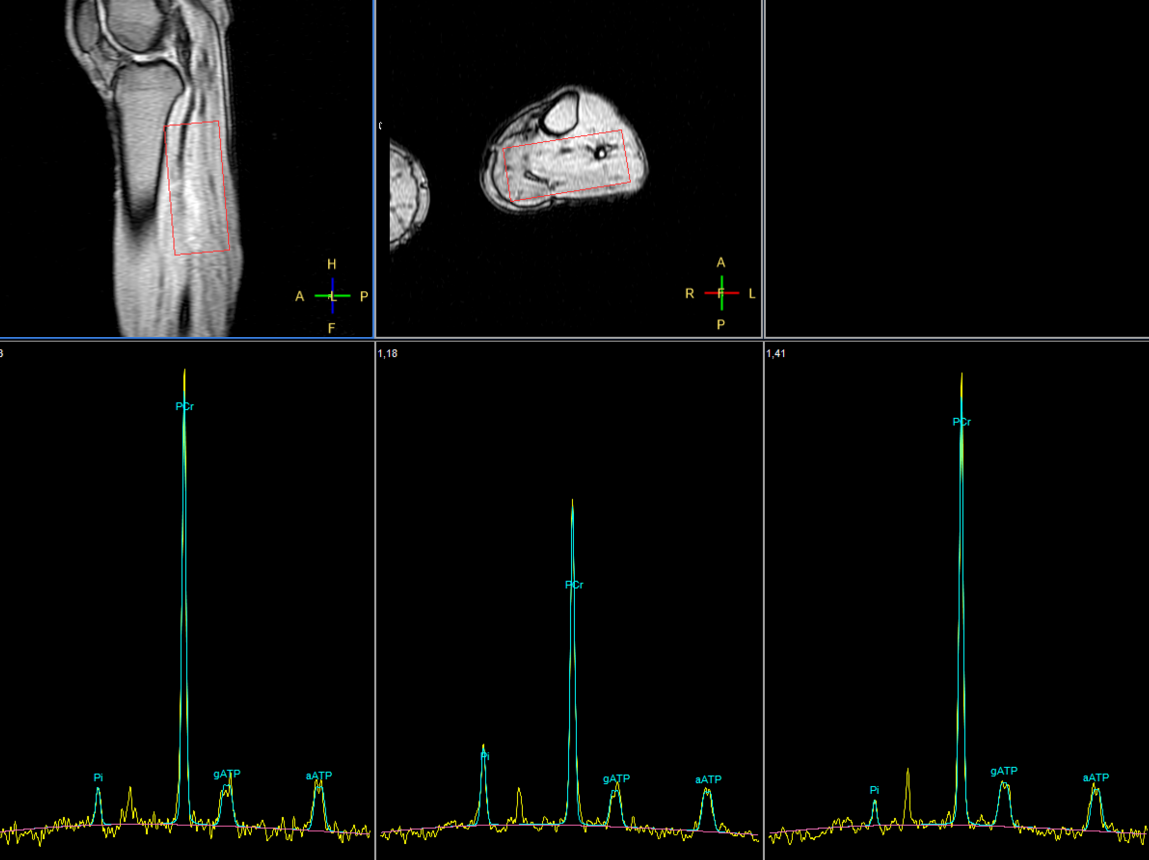

31P Phase Acquired (5 sec/acq, 50 dynamics)

31P Phase Acquired (Rest - Stress - Recovery)

31P Phase Acquired (Rest)

31P Phase Acquired (Stress)

31P Phase Acquired (Recovery)